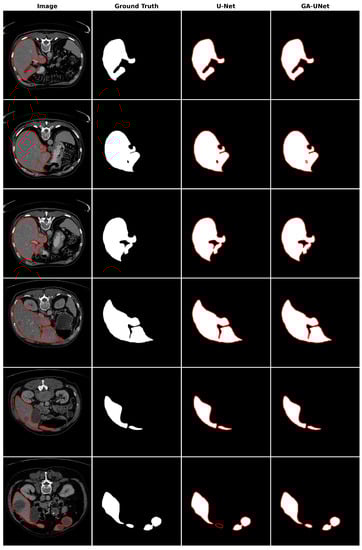

For the qualitative analysis, we show some precise and promising segmentation results in Figure 8 to visually compare our method with the original U-Net [12] model. The lung segmentation result depicted in Figure 8 is deemed satisfactory, as the proposed approach GA-UNet was able to almost completely segment the lung from the CT scan images. But in some instances, as shown in rows 2 and 4, it missed a small portion of the lung.

Figure 8.

Segmentation results on lung segmentation dataset. From left to right, the columns represent in order: the input image, ground truth, U-Net prediction, and GA-UNet prediction. The red curves represents the actual area of the lung.